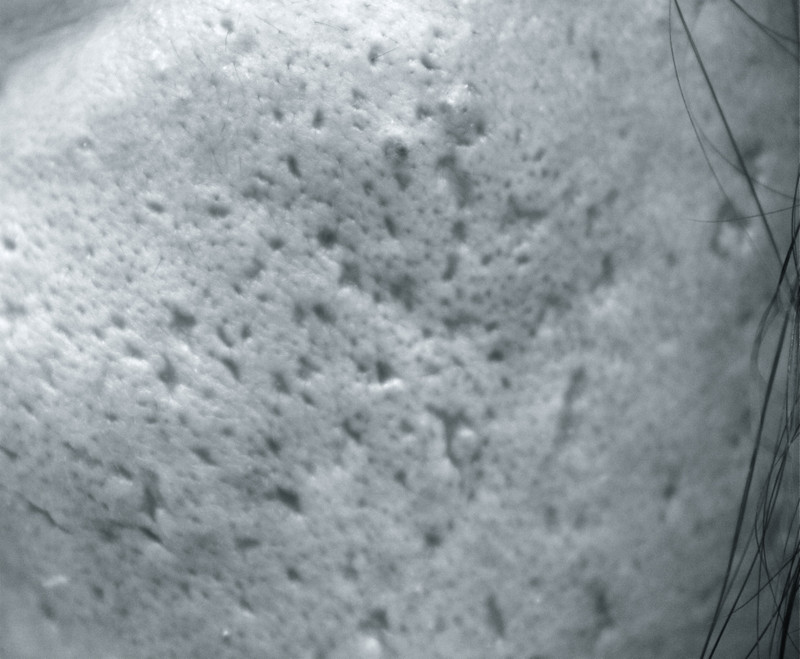

すなわち、ニキビ瘢痕(下写真)には予防しかないということなんですweepニキビは、何度治療しても再発するかもしれませんが、とにかく放置しないことが凄く大切なんですconfident

Img_2334